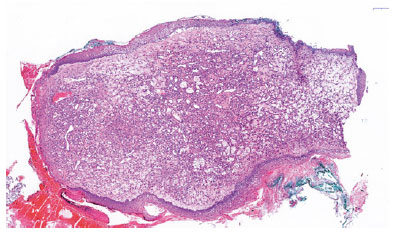

The 12 × 6 × 4 mm3 lesion had a nodular appearance on macroscopic examination. The lesion was covered with stratified squamous epithelium and conjunctival mucosa (Figure 3). The underlying fibrous stroma had numerous small vascular structures with a narrow lumen. Some extravasated erythrocytes were present inside the lesion. Ulcerated areas with some neutrophils were seen in the covering epithelium. The vessels showed strong CD31 expression in immunohistochemical staining (Figure 4). Kaposi sarcoma was excluded due to negative HHV-8 staining. These findings were diagnostic for pyogenic granuloma.